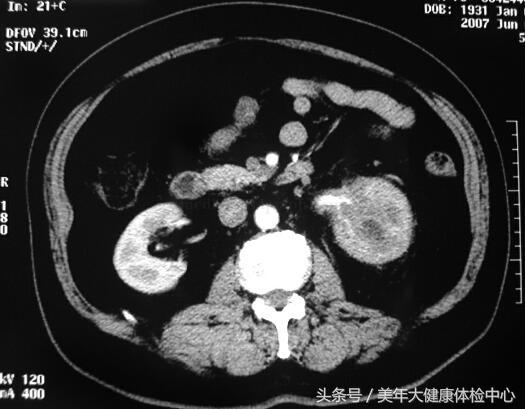

CT(图13-1):平扫左肾中上极病变,肾皮髓质分解不清、包膜不锋利,肾周脂肪囊增厚,左肾门肾盂结构不清,左输尿管上段实变。增强扫描病变无明显强化,病变边界不清。

图13-1 CT平扫